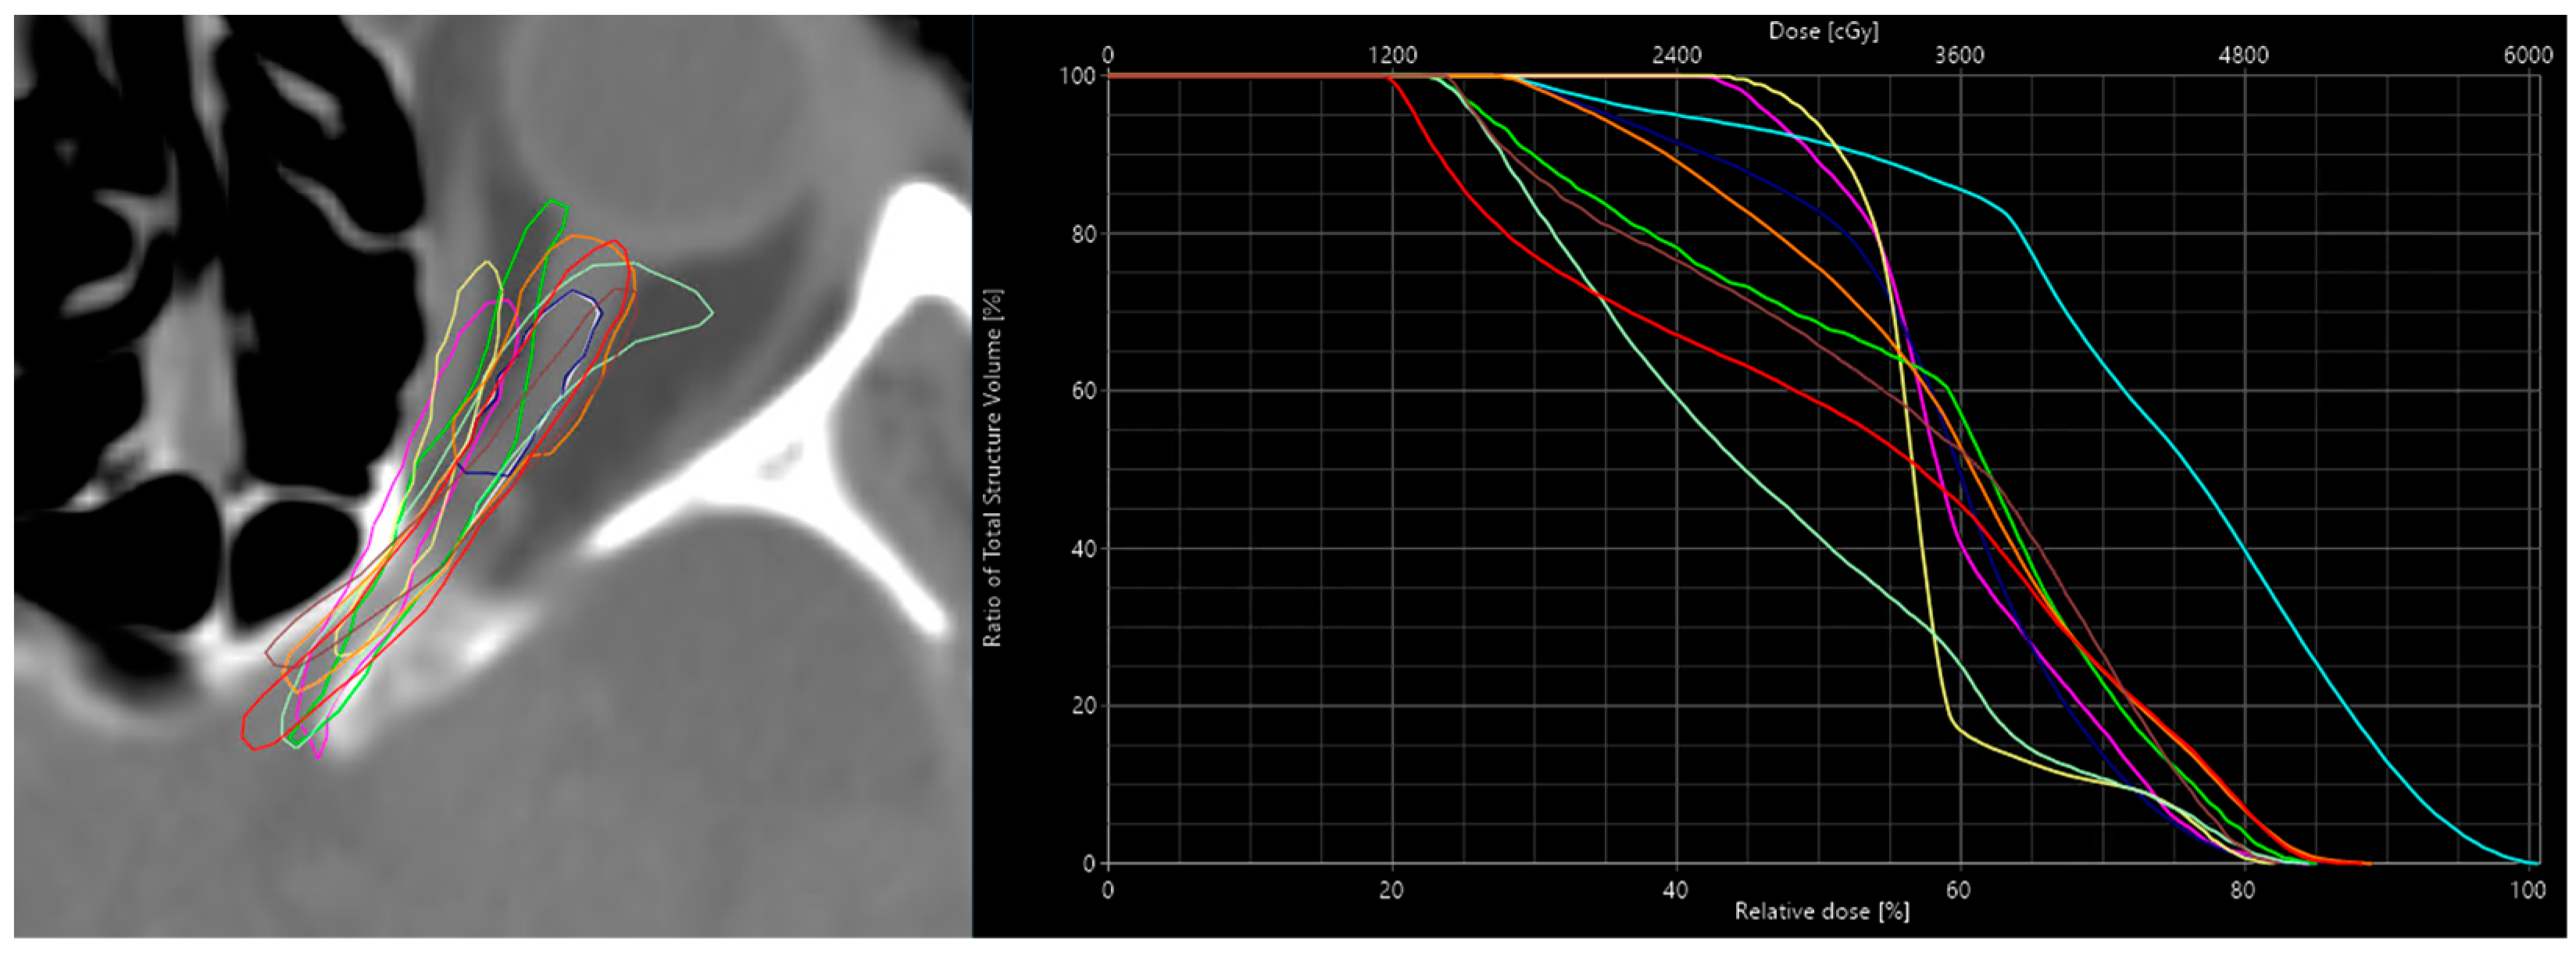

3.1. Results for Sensitivity

| ONL Contour | Calc. Dose | Pred. Dose | Δ Dose Calc-Pred | DSC | Δ to Calc-Ref | Δ to Pred-Ref |

|---|---|---|---|---|---|---|

| Reference | 34.7 | 35.5 | −0.8 | n.a. | n.a. | n.a |

| Alternative-1 | 32.2 | 35.7 | −3.5 | 0.31 | −2.5 | 0.2 |

| Alternative-2 | 30.7 | 32.4 | −1.7 | 0.26 | −4 | −3.1 |

| Alternative-3 | 34.2 | 34.5 | −0.3 | 0.63 | −0.5 | −1 |

| Alternative-4 | 31.8 | 34.1 | −2.3 | 0.59 | −2.9 | −1.4 |

| Alternative-5 | 26.9 | 30.1 | −3.2 | 0.51 | −7.8 | −5.4 |

| Alternative-6 | 32.8 | 36 | −3.2 | 0.20 | −1.9 | 0.5 |

| Alternative-7 | 41.8 | 41.2 | 0.6 | 0.16 | 7.1 | 5.7 |

| Alternative-8 | 35.3 | 33.1 | 2.2 | 0.58 | 0.6 | −2.4 |

| Alternative-9 | 34.5 | 36.1 | −1.6 | 0.05 | −0.2 | 0.6 |

| Mean | 33.49 | 34.87 | −1.38 | 0.37 | Corr. Coeff.: 0.89 | |